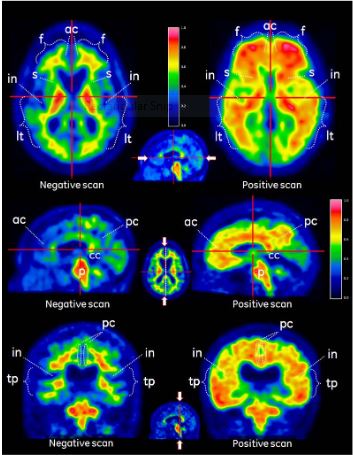

Les images PET doivent être lues à l’aide d’une échelle de couleurs Sokoloff, Rainbow ou Spectrum. L’évaluateur doit comparer l’intensité du signal de la substance grise corticale par rapport à l’intensité maximale du signal de la substance blanche. Les images doivent être visualisées de manière systématique (Figure 1) en commençant au niveau du pont (p) et en défilant vers le haut:

·Lobes frontaux et cortex cingulaire antérieur (f, ac, analyse axiale)

·Cortex cingulaire postérieur et précunéus (pc, analyse sagittale)

·Aspects des zones temporo-pariétales incluant l’insula (in, analyse axiale et tp-in, analyse coronale)

·Lobes temporo- latéraux (lt, analyse axiale)

·Région striatale (s, analyse axiale)

L’interprétation des images se fait visuellement, en comparant l’activité dans la substance grise corticale et l’activité dans la substance blanche adjacente.

·Une région est considérée comme ayant une fixation négative (normale) si le signal du traceur est faible dans les régions corticales (intensité du signal nettement inférieure comparée à la substance blanche adjacente et similaire en intensité aux régions riches en substance grise du cervelet). Le signal ne sera pas complètement absent dans les régions de la substance grise, car la fixation de la substance blanche déborde sur les régions de substance grise du fait de l’effet de volume partiel lié à la résolution des caméras PET.

·Une région est considérée comme positive (anormale) si le signal du traceur dans les régions corticales semble élevé (d’une intensité environ égale ou supérieure à celle de la substance blanche adjacente et supérieure aux régions riches en substance grise du cervelet).

·Si l’une de ces régions est clairement positive (anormale), l’image doit alors être classée positive (anormale). Sinon, elle doit être classée négative (normale).

Figure 1

Cas de PET avec VIZAMYL montrant des exemples d’examens PET au flutémétamol (18F) négatifs (gauche) et positifs (droite). Les vues axiales (première ligne), sagittales (seconde ligne) et coronales (troisième ligne) sont représentées.

Figure 1. Vues axiales (a), sagittales (b) et coronales (c) d’images négatives et positives avec le flutémétamol (18F) (gauche et droite respectivement). Les images négatives montrent le motif sulcogyral de la substance blanche alors qu’il n’est pas discernable sur les images positives à droite. Noter l’intensité plus élevée (>60 % du maximum) dans la substance grise des images positives comparativement aux images négatives et l’extension radiale de l’intensité vers le bord convexe nettement défini des faces latérales. Les images négatives présentent une intensité dégressive vers la périphérie des tissus. Il faut noter également dans les régions médiales un plus haut niveau d’intensité dans la substance grise sur les images positives à droite.

Légende: Substance grise – f frontal et ac cingulaire antérieur, pc cingulaire postérieur et précunéus, lt temporo-latéral, tp temporo-pariétal, in insula et s striatum. Substance blanche – p pont et cc corps calleux.